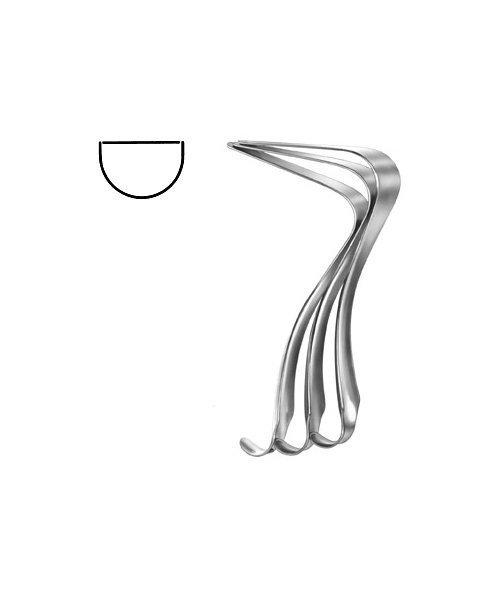

- Gynecology, Surgical Instruments

Endocervical Speculum

- Size : 34.5 CM - 13 1/2"

- Read more